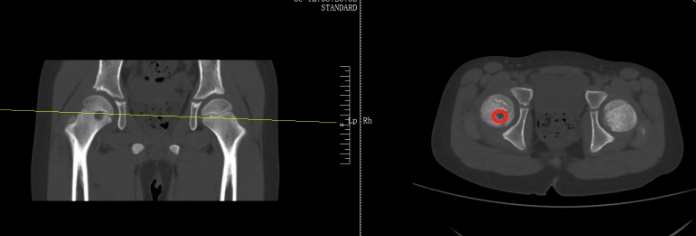

检查后,医生发现,肿瘤直径约有20厘米,基本占满了女孩的右侧屁股,万幸还未出现远处转移,可以通过手术将肿瘤剥离。

当地医生诊断为右股骨近端占位,怀疑内部可能长了肿瘤。扬扬妈妈听到医生的话心里直害怕,夫妻两人又马不停蹄带孩子来到了骨科医院进一步检查,扬扬被确诊为右股骨近端肿瘤。

好在从影像上来看,初步考虑是偏良性。在跟家长商讨过后,医生为扬扬执行了前侧入路右侧股骨头钻取刮除、取自体髂骨骨移植术,手术顺利切除病灶,并补上了股骨的“漏洞”。